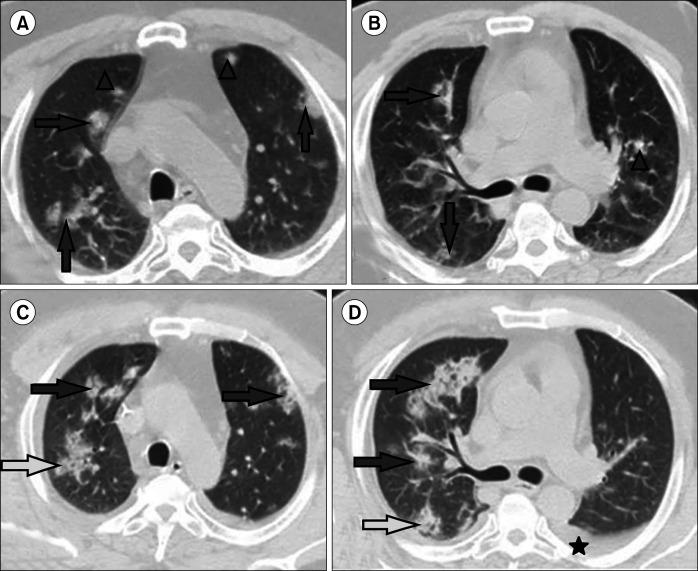

Data on the association between coronavirus disease 2019 (COVID-19) and the epidemiology and outcomes of hematological malignancies are limited. Hence, the present study aimed to assess the imaging findings using chest multidetector computed tomography (MDCT) in patients with hematologic malignancies who developed COVID-19 pneumonia.

This retrospective study included two groups, the first group consisted of COVID-19 infected patients with hematologic malignancies (100 patients), while the second group consisted of COVID-19 infected patients without hematologic malignancies or other comorbidities (100 patients). The hematological malignancies included in this study were non-Hodgkin's lymphoma (40 patients), acute myeloid leukemia (25 patients), chronic lymphocytic leukemia (15 patients), multiple myeloma (10 patients), Hodgkin's lymphoma (8 patients), and myelodysplastic syndrome (2 patients). Chest multidetector CT imaging was performed in all patients to assess for ground-glass opacity, consolidation, pleural effusion, and airway abnormalities.

More than one CT finding was reported in each patient. No significant difference was observed in the ground-glass opacities (=0.0594), nodule formation (=0.2278), or airway thickening/dilatation (=0.0566) between the two groups; meanwhile, a significant difference was observed in the degree of consolidation, the number of lobes affected, and pleural effusion (=0.0001) as well as in the total lung severity (=0.0001); minimal, mild, and severe affection rates; and (=0.0047) moderate affection rates.

Early and reliable diagnosis of lung disease in COVID-19-infected patients may be achieved through multidetector CT imaging. Patients with hematological malignancies are more likely to have severe COVID-19 pneumonia, and radiologists should recognize the CT characteristics of this infection.